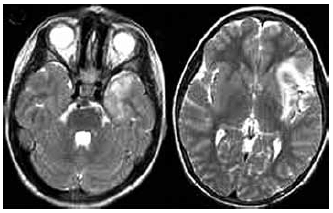

Feminina, 42 anos, admitida no pronto-socorro com história de febre não aferida e confusão mental de início há 3 dias. Enquanto aguardava para ser atendida, apresentou um episódio de crise convulsiva generalizada. Ao exame neurológico, apresentava confusão mental, agitação psicomotora e rigidez de nuca. O exame de neuroimagem encontra-se abaixo.

Exame de líquor mostrou pressão de abertura de 22 mmH20, celularidade de 25 com predomínio de linfócitos, proteinorraquia de 15 mg/dL e glicorraquia de 50 mg/dL. De acordo com este quadro clínico, assinale a alternativa correta.